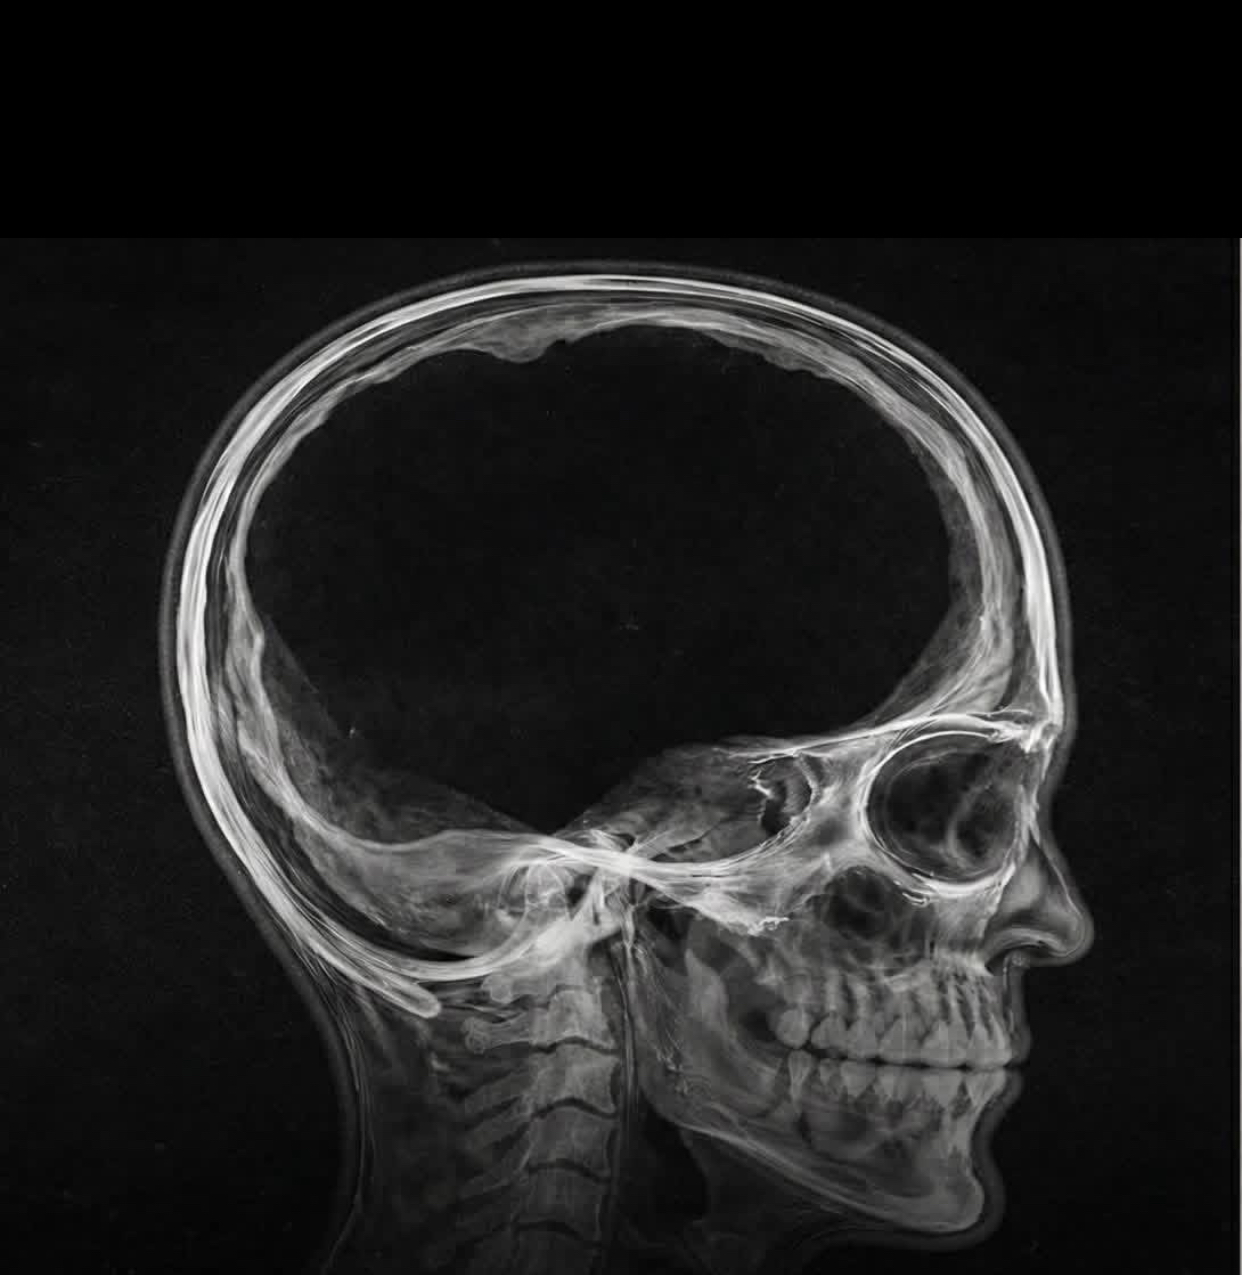

هل يمكن للإنسان أن يعيش حياة طبيعية، يتزوج، ينجب أطفالاً، ويذهب إلى وظيفته يومياً، وهو يفتقد 90% من كتلة دماغه؟ الصورة التي تراها بالأعلى ليست مشهداً من فيلم خيال علمي، بل هي توثيق لواحدة من أغرب الحالات الطبية التي حيرت العلماء في العصر الحديث.

عندما أجرى الأطباء فحوصات الرنين المغناطيسي والأشعة المقطعية للبحث عن سبب ألم الساق، أصابتهم الدهشة. الصور أظهرت جمجمة شبه فارغة!

لم يكن دماغ الرجل “مفقوداً” بالمعنى الحرفي، بل كان مضغوطاً بشكل لا يصدق. لقد عانى هذا الرجل منذ طفولته من حالة تسمى “استسقاء الرأس” (Hydrocephalus)، وهي تراكم السوائل داخل تجاويف الدماغ.

على مدى عقود، وبشكل بطيء جداً، تضخمت هذه التجاويف المليئة بالسائل، وضغطت أنسجة الدماغ الحيوية نحو الخارج حتى أصبحت مجرد طبقة رقيقة جداً ملتصقة بجدار الجمجمة الداخلي. لقد تبقى لديه فعلياً ما يقارب 10% فقط من الكتلة الدماغية الطبيعية.